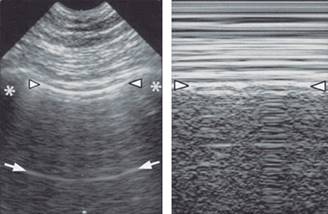

La línea pleural, que se encuentra entre dos costillas y dando el signo de murciélago, indica la pleura parietal (y por lo general visceral). El pulmón deslizante es una reluciente línea pleural, produciendo en el modo M el signo de la orilla del mar. Las líneas A son repeticiones de artefactos horizontales de la línea pleural que aparece a intervalos regulares. El segundo artefacto principal, son las líneas B, que se puede observar en individuos normales en algunas áreas estandarizadas (Figura 1).

La línea B es un artefacto con siete criterios (los tres primeros constante y los cuatro últimos bastante constante): cola de cometa, que surgen de la línea pleural, que se mueven con deslizamiento pulmonar, bien definido, de largo, hiperecoico y con borrado de una líneas (Figura 2).